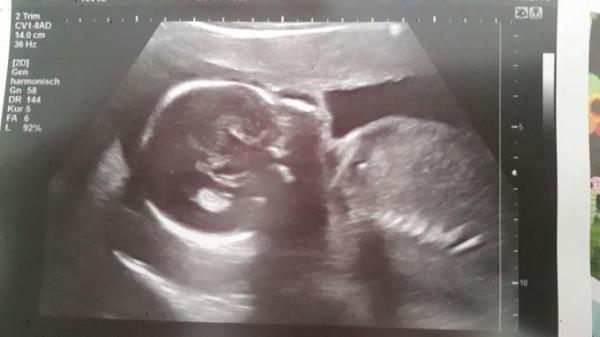

ROSA.... Seit heute ist's dann amtlich... :) Hatte heute Vorsorge und hab mir den Luxus vom Baby-TV gegönnt. Haben schöne Bilder gemacht. Und selbst ich kenne auf den ersten Blick erkennen, dass das ein Mädel wird. :) Unsere Große war erst etwas enttäuscht. Sie hatte sich doch einen kleinen Bruder gewünscht. Aber mittlerweile ists ok. Die Kurze ist 26cm groß und wiegt ca 405 g.

Bild zu Wir gehören zu Team - Forum für August - Mamis